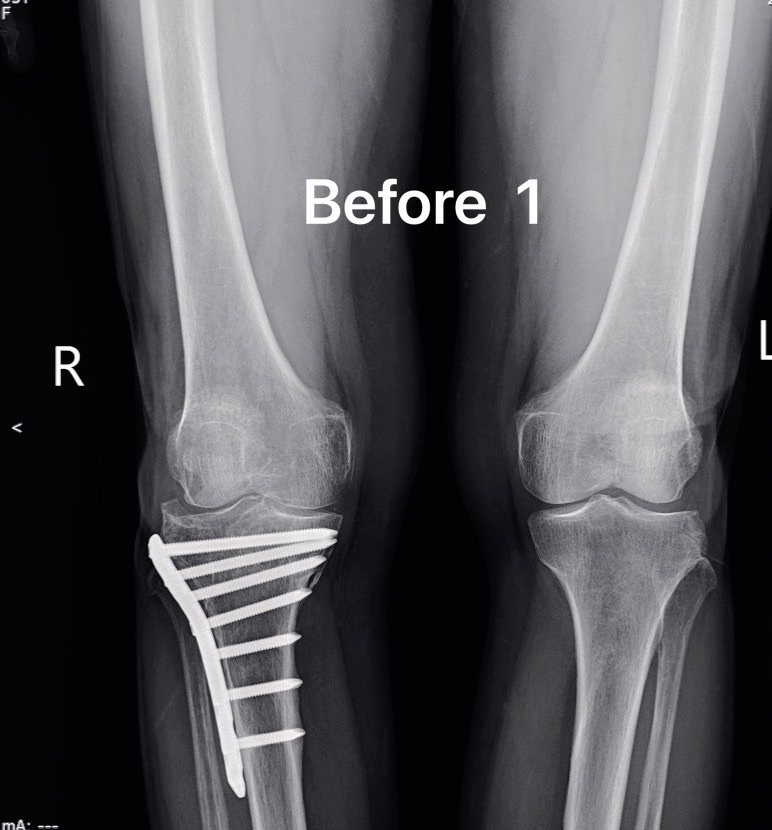

รวมภาพ X-ray Before/After Total Knee